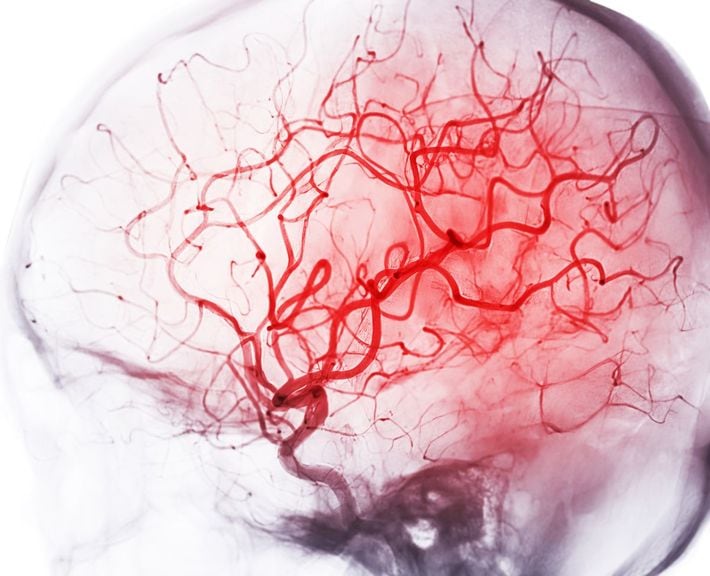

※写真はイメージです